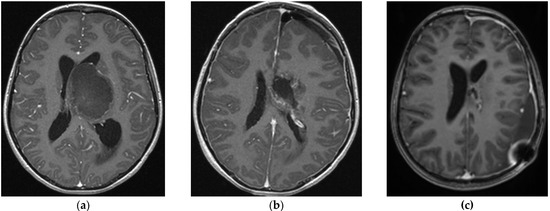

| Case # | Age y/o | Histology | Grade of Resection | Adjuvant Treatment | Complications | Follow Up in Months | Recurrence | Clinical Status |

|---|---|---|---|---|---|---|---|---|

| Low Grade | ||||||||

| 1 | 9 | Pilocytic astrocytoma | GTR | No | No | 96 | No | ANED |

| 2 | 17 | Pilocytic astrocytoma | GTR | No | No | 84 | No | ANED |

| 3 | 7 | Pilocytic astrocytoma | GTR | No | No | 12 | No | ANED |

| 4 | 15 | DNET | GTR | No | No | 60 | No | ANED |

| 5 | 4.6 | Pilocytic astrocytoma | GTR 2× | No | No | 40 | Yes | ANED |

| 6 | 16 | Pleomorphic xanthoastrocytoma | STR | No | No | 42 | No | ASD |

| 7 | 11 | Pilocytic astrocytoma | GTR | No | No | 18 | No | ANED |

| 8 | 5 | Ganglioglioma | STR | No | No | 16 | No | ASD |

| High Grade | ||||||||

| 9 | 18 | Astrocytoma WHO gr. 4 | GTR | CR * | No | 21 | Yes | DOD |

| 10 | 15 | Mut. diffuse midline glioma | STR | CRI * | Hydrocephalus—VP drainage | 15 | Yes | DOD |

| 11 | 11 | Mut. diffuse midline glioma | GTR | CRI * | Hydrocephalus—VP drainage | 6 | No | ANED |